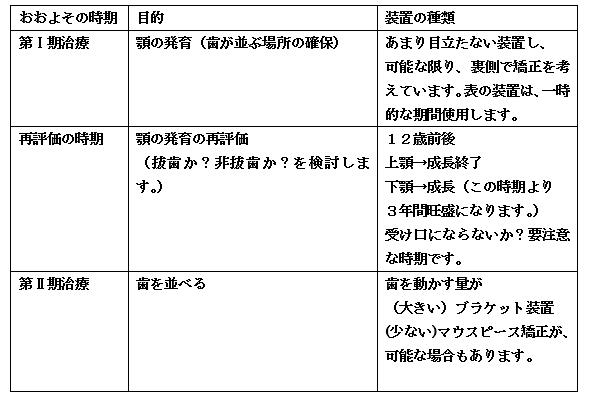

こども矯正